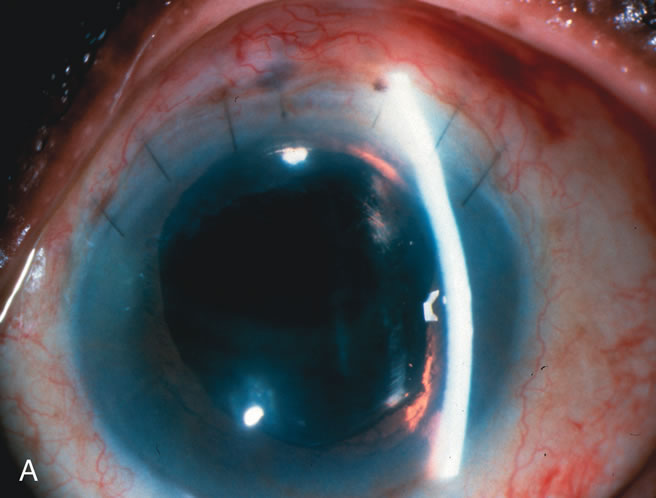

Fig. 1. The anatomic advantage of small incision cataract surgery for the glaucoma patient. A. Long-term bleb function with a large cataract incision is difficult to achieve with either ECCE-trabeculectomy or trabeculectomy followed later by ECCE. This bleb failed to form sufficiently when combined with large incision ECCE. The inflammation, bleeding, and long-term wound healing with stimulation of fibroblasts associated with this technique are more likely to cause bleb failure. In addition, the increased iris manipulation necessary to deliver the nucleus and subsequent iris repair adds to the long-term breakdown of the blood aqueous barrier. B and C. Two-site phacotrabeculectomy has the advantage of small incision cataract surgery combined with separate site trabeculectomy. The incision size is one third the size of the standard ECCE. The inflammation is less severe, and cataract wound healing is confined to the temporal area. Visual rehabilitation with phacoemulsification and foldable IOL is much faster. Phacoemulsification allows successful lens extraction even in the unfriendly environment of a smaller pupil compared with ECCE. The trabeculectomy is performed in an entirely different site, well away from the wound healing associated with temporal phacoemulsification. The likelihood of this filter functioning long-term is greater than with ECCE-trabeculectomy. D. The surgeon also has the option of single-site phacotrabeculectomy with foldable IOL. Both the lens extraction and trabeculectomy are performed through one small 3.5-mm limbal incision.

In years past, patients with both cataract and glaucoma frequently provided overwhelming surgical challenges for the ophthalmologist. The ability to carry out phacoemulsification through a 3.2-mm corneal incision along with inserting a foldable IOL is a vast improvement over 11-mm incisions that were common a decade ago (Fig. 1). The anatomical and inflammatory changes to the eye are less with small incision techniques, improving the likelihood of success with concomitant glaucoma surgery. Pharmacologic inhibition of fibrosis along with postoperative wound revision increases the long-term success rate of filtration surgery when combined with lens extraction. (Fig. 2). The learning curve may be steep at times, but the blending of cataract and glaucoma surgical skills slowly falls into place as the surgeon constantly learns and upgrades his or her technique.